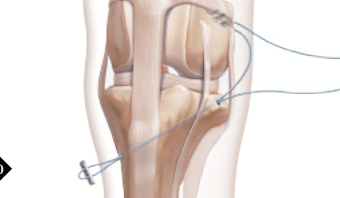

Extra-Capsular Stabilization - additional information

While the patient is still anesthetized, the patient is taken into radiology for post-surgery radiographs (X-rays). The radiographs are assessed to ensure the apparatus FASTak screw and toggle are appropriately positioned.